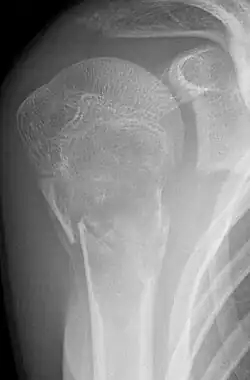

Pathologische Fraktur bei Juveniler Knochenzyste (Humeruskopf)

• Einfache (juvenile) Knochenzyste: Gutartige, primär einkammerige, flüssigkeitsgefüllte Höhle, meist im metaphysären Markraum. Wird meist erst durch Spontanfraktur auffällig. Klassisches Röntgenzeichen ist das Fallen-Fragment-Sign.

Eine Knochenzyste ist eine gutartige tumorähnliche Knochenläsion, welche einen flüssigkeitsgefüllten und z. T. zellgefüllten Hohlraum im Knochen darstellt. Radiologisch erkennt man hier im Röntgenbild eine ein- oder mehrkammerige Aufhellung. Die Zysten im jugendlichen Knochen werden meist als Zufallsbefund beim Röntgen nach Unfallverletzung oder als Ursache von sogenannten pathologischen Frakturen (Frakturen bei verringerter Knochenfestigkeit) entdeckt.